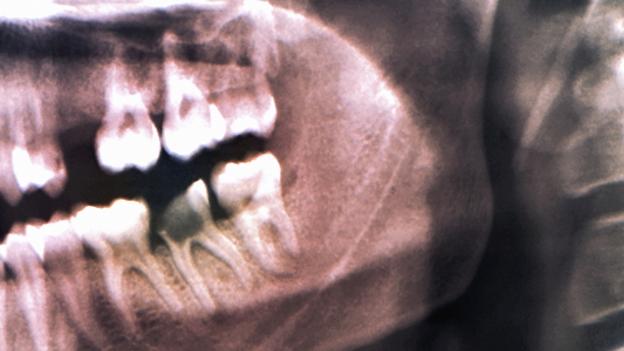

The guy who says google old roman practices is correct and also incorrect the romans did have extraction methods but they also had a very high carb diet. Does anyone know whether this affects the second teeth im pretty sure it does with regards to their position etc. The latest research has suggested that wisdom teeth became increasingly problematic rather than useful after human populations settled into an agrarian model of food production and social structure.

What did they do. What did people do to pull teeth before. The first reason teeth were pulled was because we had no way to treat gum disease.

Did braces change your face a lot. Nothing but the tooth. The second reason teeth were pulled was because dentists were barbers or blacksmiths and just yanked the offending problem tooth.

The third reason teeth. Your teeth and they come in and crowd the others its not a happy day.